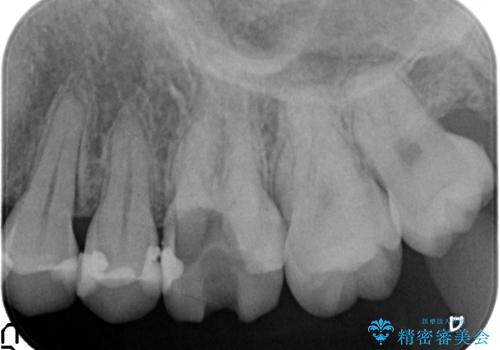

- 左上の奥歯が痛んでものを食べられないといらっしゃった方の症例です。

左上6は虫歯を除去後、神経症状がないことを確認し、オールセラミッククラウンによる補綴を行いました。

左上5は古い樹脂と虫歯を除去後、セラミックインレーによる修復を行いました。